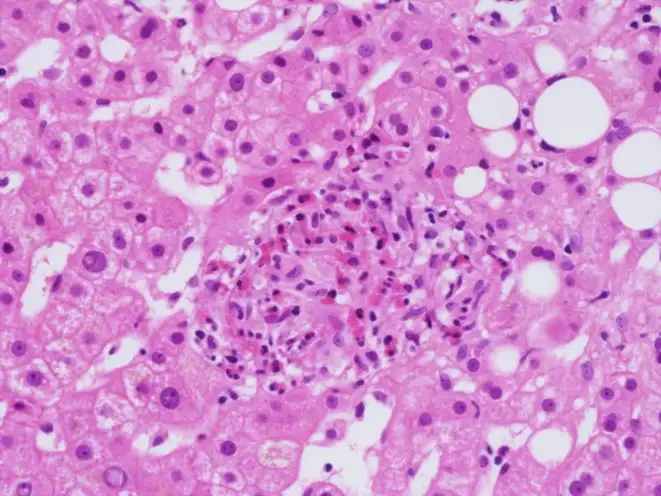

当伯内特考克斯氏体进入人体后,它的入侵策略堪称完美。它主要通过呼吸道进入,被肺泡巨噬细胞吞噬——这本应是免疫系统的第一道防线,但这种细菌却将吞噬作用变成了入侵的通道。细菌进入巨噬细胞后,被包裹在一个叫做吞噬体的膜结构中。正常情况下,吞噬体会与溶酶体融合,溶酶体内的酸性环境和消化酶会将入侵者彻底摧毁。但伯内特考克斯氏体进化出了一个惊人的对策:它不仅不逃避这种融合,反而主动促进它。它需要的正是溶酶体的酸性环境。

这种细菌携带的酸性磷酸酶可以中和吞噬体的杀伤性物质,同时它利用宿主细胞的营养在酸性的吞噬溶酶体中繁殖。这个特殊的结构被称为"考克斯氏体包含泡"(CCV)。在这个改造过的细胞器内,细菌开始疯狂复制。它们会产生一种特殊的Dot/Icm型IV型分泌系统,向宿主细胞注射数百种效应蛋白,操纵宿主细胞的信号通路,阻止细胞凋亡,确保自己的生存和繁殖。当细菌数量达到一定程度时,包含泡会膨胀到几乎充满整个宿主细胞,最终导致细胞破裂,释放出数百个新的细菌,每个都可以感染新的细胞。